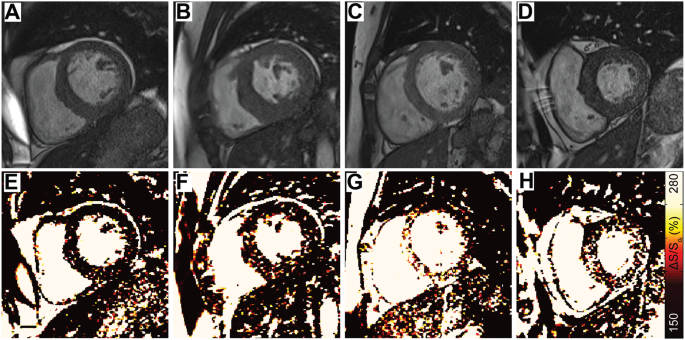

Various spatial patterns of elevated ΔS/So were observed among hypertrophic patients with ESRD. (A–D) Representative end diastolic images acquired using a 45° excitation flip angle at the mid-ventricle are shown for 4 hypertrophic patients with ESRD. (E–H) Corresponding ΔS/So maps reveal different patterns and magnitudes of ΔS/So elevation despite the common structural feature of hypertrophy. An expanded version of this figure including 12 patients can be found in the Supplemental Data.

No correlation was observed between divergence and either concomitant diastolic strain rate (ρ = 0.06, p = 0.646) or GLS (ρ = 0.02, p = 0.910, Fig. 5). A moderate correlation was evident when comparing heightened divergence with increased LVMI (ρ = 0.31, p = 0.014, Fig. 5) and septal thickness (ρ = 0.27, p = 0.035). However, many patients with ESRD and significantly elevated LVMI demonstrated normal divergence values (Fig. 5A). This relationship is further illustrated in Fig. 6 by comparison of heterogeneously elevated ΔS/So patterns in 4 patients with increased septal thickness and heightened LVMI (a larger subset are shown in Fig. S6). In contrast, increased LVMI was significantly correlated with reduced diastolic strain rate (ρ = −0.26, p = 0.043) and attenuated global longitudinal strain (ρ = 0.38, p = 0.002) across participants.